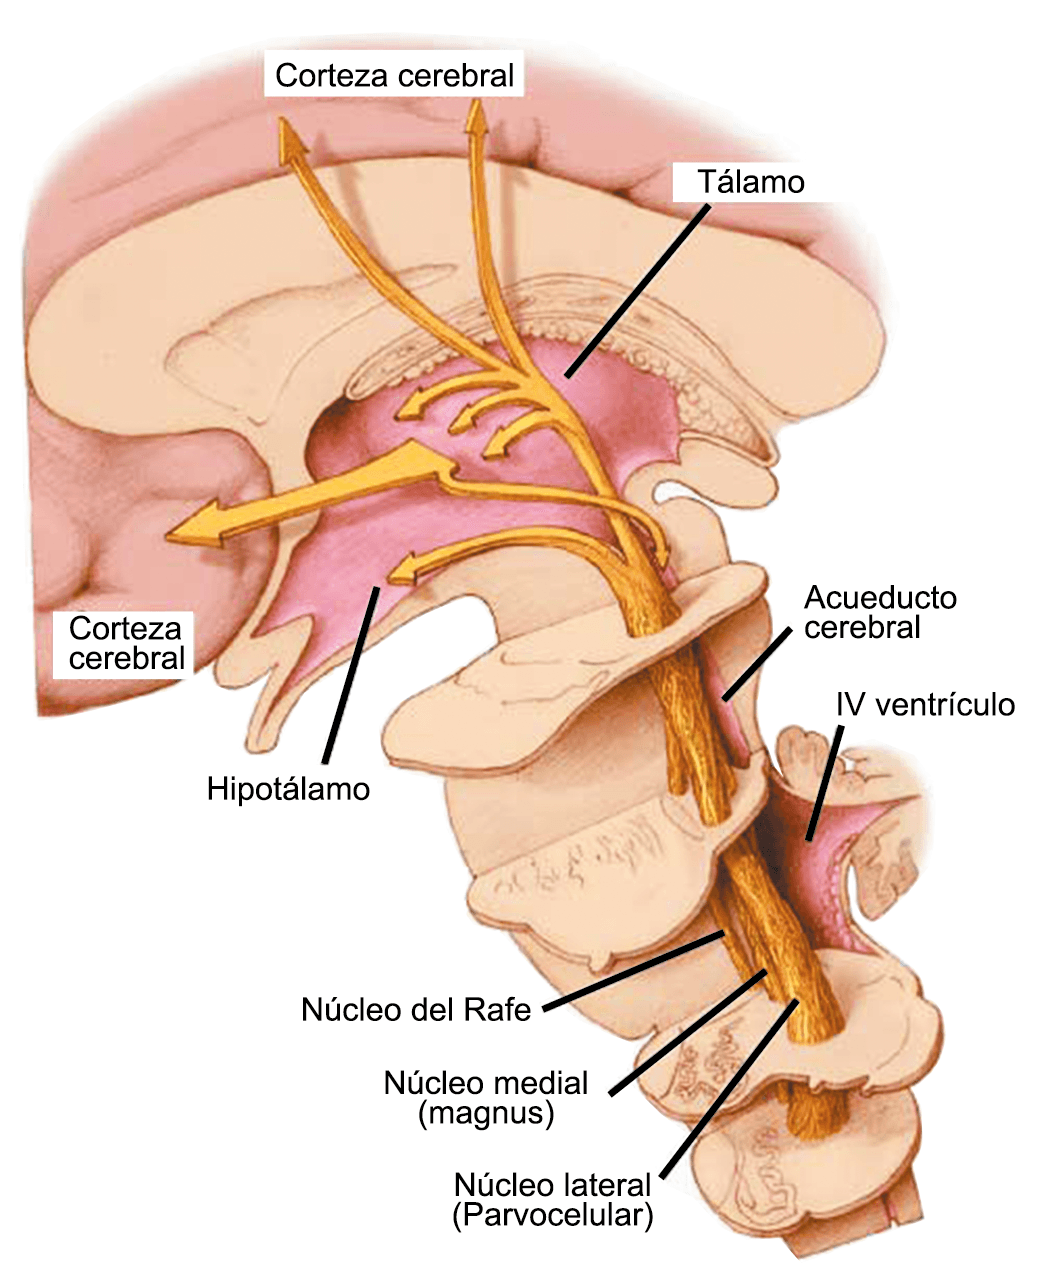

La relevancia del tronco encefálico para la fisiopatología de la migraña está respaldada por estudios clínicos e investigaciones básicas. En presencia de la crisis dolorosa, se ha demostrado que hubo un aumento del flujo sanguíneo cerebral en el mesencéfalo, la protuberancia rostral dorsal cerca del PAG y los núcleos del rafe(22) y además se localizaron varios síntomas de migraña en diferentes áreas del cerebro concomitantemente con la experiencia de dolor de cabeza en la corteza cingulada, fotofobia en la corteza de asociación visual y fonofobia en el auditivo, corteza de asociación. Estas señales desaparecieron después de la terminación exitosa del ataque. Sin embargo, el aumento de flujo sanguíneo cerebral en el tronco encefálico persistió en la fase temprana sin dolor. Por lo tanto, esta estructura refleja no solo un síntoma de migraña, sino que también indica una disfunción de importancia para la generación o el mantenimiento del ataque de migraña en sí.

Muchos pacientes también describen la privación del sueño o el sueño interrumpido o reducido continuamente, como un posible desencadenante de la migraña(50). La regulación del sueño, particularmente dentro del hipotálamo, está fuertemente ligada al desencadenamiento de la migraña. Los núcleos del mesencéfalo están involucrados al desencadenamiento de la migraña, además de contribuir a los síntomas asociados a través de proyecciones al hipotálamo y otros núcleos del tronco encefálico y diencefálico. Además de controlar la modulación del dolor, las cé- lulas “ON: ENCENDIDAS” y “Off: APAGADAS” en RVM (médula medial rostro-ventral) y NRM (nú- cleos del rafe magno) (Figura 21).

También están involucradas en el control de respuestas a estímulos externos inocuos, actividad motora y procesos homeostáticos(51). Las células “On: ENCENDIDAS” están activas dependiendo del estado durante las horas de vigilia, pero no durante la alimentación y la micción, o durante el sueño, mientras que las células “Off: APAGADAS” están activas durante el sueño y activas durante la vigilia solo antes de micción, así como durante la alimentación. Por lo tanto, la activación de células “Off: APAGADAS”, durante el sueño, la alimentación y la micción, evita que respondan a estímulos inocuos e incluso nocivos agudos, mientras que durante la vigilia la activación de células “On: ENCENDIDAS” facilita el estado de alerta a los estímulos sensoriales. Además, la vlPAG (Área ventrolateral de la sustancia gris periacueductal) (Figura 22) participa en los mecanismos de excitación, a través de la activación de las neuronas dopaminérgicas durante la vigilia y la inactivación de estas neuronas durante el sueño. En el contexto de los posibles desencadenantes de la migraña, la privación del sueño es un proceso homeostático que da como resultado respuestas neuronales específicas en la vía PAG-RVM, en particular, la activación de las células “ON” y la inhibición de la activación de las células “OFF”.

El dolor de la migraña es, sin duda, una consecuencia de la activación o la percepción de la activación de los mecanismos neurovasculares, de allí que sea considerado un trastorno puramente neuronal. Mucha evidencia indica que los cerebros de las personas con migraña pueden ser diferentes en la forma en la cual responden a la estimulación sensorial, incluso interictalmente(102). Una hipótesis alternativa y que lo abarca todo es que el cerebro está en el centro del desencadenamiento de la migraña. Más que una activación secuencial de diferentes regiones del cerebro, la migraña es un trastorno del cerebro y por lo tanto, se considera un “estado cerebral”, que es una consecuencia de cambios o disfunciones en las regiones del tronco encefálico y el hipotálamo, que contribuyen a su vez a cambios a nivel celular y vascular en muchas regiones del cerebro. Esta hipótesis establece que la migraña puede describirse mejor como una consecuencia de la disfunción en el tronco encefálico y los núcleos hipotalámicos que normalmente modulan o activan las entradas sensoriales, como el tacto, la luz, los sonidos y los olores. Estos núcleos del tronco encefálico y del hipotálamo pueden considerarse “mediadores de la migraña” y su disfunción puede llevar al fracaso de los mecanismos de integración y filtrado cerebrales, lo que da como resultado la percepción de activación de los sistemas sensoriales en condiciones normales. La compleja red de conexiones entre las regiones del tronco encefálico, que incluyen PAG, RVM, locus ceruleus y SuS y los núcleos diencefálicos, incluidos el hipotálamo, el tálamo y la corteza, pueden conducir a la generación de síntomas a través de la misma disfunción central. La disfunción en estas regiones, a través del control descendente del tráfico nociceptivo trigeminovascular, puede conducir a la percepción del dolor de cabeza a través de la palpitación de los vasos normales y la disfunción continua puede conducir a la sensibilización central de las neuronas trigeminovasculares y la exacerbación del dolor con la actividad física normal, así como en la piel: alodinia cefálica y extracefálica. La convergencia de entradas sensoriales en el tálamo que se proyectan a la corteza puede explicar la hipersensibilidad a la luz, los sonidos y los olores. La misma disfunción puede conducir a cambios homeostáticos, controlados por el hipotálamo, relacionados con el sueño, la alimentación y la actividad. La alteración general de la función cortical y subcortical puede desencadenar eventos como el aura migrañosa y extenderse a una incapacidad general para funcionar correctamente. Los factores genéticos heredados juegan claramente un papel en la predisposición a la susceptibilidad a la migraña, al igual que el papel de los desencadenantes potenciales de la migraña, cuyo vínculo común parece jugar en el corazón de la homeostasis cerebral en el hipotálamo y el tronco encefálico. (figura 7).